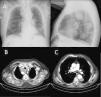

A 76-year-old man was referred from the emergency department due to radiological changes. Background of interest included work in a coal mine for 9 years, former smoking habit (90 pack-years), a diagnosis of COPD treated with umeclidinium/vilanterol, and intermittent claudication. Reported symptoms were mMRC grade 2 dyspnea on exertion, unchanged in the last year. The only finding on examination was reduced breath sounds in both lung fields. Imaging tests (Fig. 1) showed mediastinal widening with images significant for masses. A chest CT scan was requested.

(A) PA and lateral chest X-ray showing mediastinal widening with images significant for masses. (B) Chest CT with intravenous contrast, showing an aberrant right subclavian artery that originates in the aortic arch distal to the left subclavian artery, running behind the esophagus towards the right side, with a large, partially thrombosed aneurysm. (C) Partially thrombosed aneurysm of the descending aorta.

Subclavian artery aneurysms are rare entities, representing 0.01% of peripheral aneurysms.1 They are usually due to arteriosclerosis but are sometimes caused by trauma or degenerative diseases. Clinical manifestations are rare, and diagnosis is more common after an incidental finding simulating a lung mass on chest X-ray. Chest CT is a useful technique for differential diagnosis of this entity. Aneurysms can sometimes rupture, provoking a life-threatening situation that requires surgical intervention.2